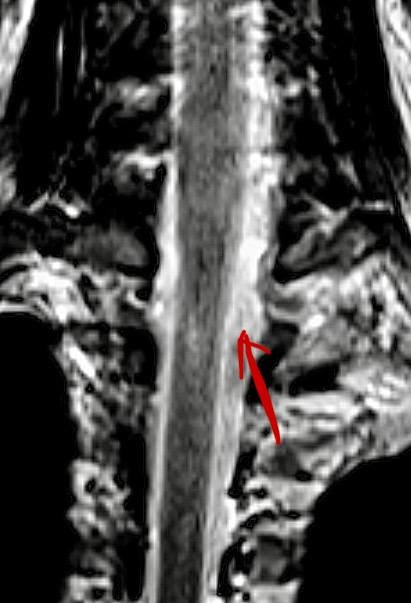

Пациентка, 29 лет.

С детства у неё была врождённая аномалия позвоночника — синдром фиксированного спинного мозга. Обычно такой диагноз выявляют и оперируют ещё в детстве, но в этом случае заболевание долго оставалось незамеченным и было диагностировано только во взрослом возрасте.

Со временем появились симптомы:

— боли в спине

— неврологические жалобы

— ухудшение качества жизни

После обследования принято решение об операции.

Выполнена операция: микрохирургическое иссечение фиксированной терминальной нити.

Цель операции — освободить спинной мозг от натяжения, остановить прогрессирование симптомов и улучшить качество жизни пациентки.